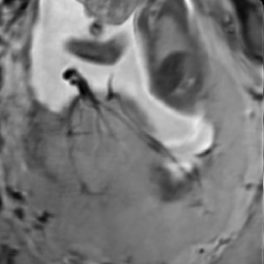

Reconstruction of Fetal Organs: Exemplary PVR and SVR reconstructions under motion introduced by kicking of the fetus are shown in Fig. 11. PVR reconstruction results show an improved visual appearance and less blurring in the region with severe motion artifacts (arrow). An example of a challenging clinical case with a kidney malformation in one of twin fetuses, is shown in Fig. 8. Our clinical partners confirmed that such complications are easier to examine and to quantify after PVR-based reconstruction.

Reconstruction of large-scale anatomy: MRI has also been shown to be very useful for the evaluation of the whole uterus and structures like the placenta. During both, normal and high-risk pregnancies, the whole uterine appearance and the condition of the placenta are considered to be an indicator for fetal health after birth [18]. Placental functions affect the birth weight as it controls the transmission of nutrients from the maternal to the fetal circulation [19]. However, the whole fetal body and secondary uterine parts can be inherently inconsistent. Different fetal body parts can move independently from the uterus. This makes the application of SVR and 2D-3D registration to the full uterus impossible in the presence of fetal motion and maternal respiration.

Besides, multiple births is a case where classical SVR pipelines based on preprocessing steps to identify consistent rigid regions will likely fail. The presence of multiple instances of the same fetal structure is usually not considered in previous methods. Therefore, a fully automatic motion correction method for the whole uterus, as it is presented in this paper, is very desirable and will enable the application of standard 3D image analysis techniques, e.g., [20, 21].